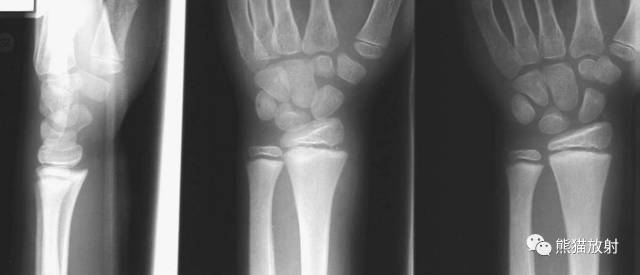

(上图)骨骺轻微向背侧、内侧移位,1-2周后随访骺板处可见成骨反应。

Salter-Harris I型:干骺端及骨骺分离

平片通常为正常,可表现为骺板增宽或骨骺轻度移位。

第一型(Ⅰ型) 骨骺分离,分离一般发生在生长板的肥大层,故软骨的生长带留在骨骺一侧,所以多不引起生长障碍;婴幼儿骺板软骨层较宽,容易发生骨骺分离,据统计,占骨骺损伤的15.9%;唯一的x线征象是骨化中心移位,该型复位容易,预后良好;而股骨头骨骺分离由于骨骺动脉多被破坏,预后不佳。该型也可见于坏血病、佝偻病、骨髓炎和内分泌疾病所致的病理性损伤。

第二型(Ⅱ型) 骨骺分离伴干骺端骨折。该型损伤最多见,占骨骺损伤的48.2%,好发部位在桡骨远端、肱骨近端及胫骨远端。多发生在10一16岁的儿童,骨折线通过肥大并累及干骺端的一部分,骨折片呈三角形,在骨折端成角之凸侧有骨膜撕裂,而凹侧骨膜完整、复位容易,预后良好。